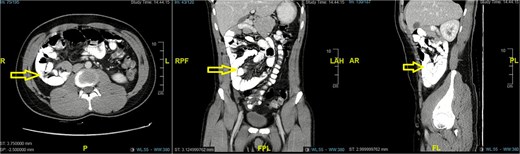

Imaging

CT abdomen showed a large right-sided paraduodenal hernia with malrotation and mildly dilated small bowel loops, with suspicion of ischemia in the terminal ileum and small fluid collection in the pelvic cavity (Fig. 3). CT revealed a right paraduodenal hernia involving Waldeyer’s fossa, characterized by a large cluster of small bowel loops located posterior and lateral to the superior mesenteric artery (SMA). A hallmark feature was the abnormally right-sided duodenojejunal (DJ) junction, indicating an associated rotational anomaly. The SMA formed the anterior margin of the hernia orifice, and the clustered loops were seen passing posterior to this vascular pedicle.

Mesenteric vessel crowding and mild swirling were present, raising concern for internal obstruction. The terminal ileum demonstrated focal wall thickening and decreased enhancement, compatible with early ischemia, and there was a small amount of adjacent pelvic free fluid.